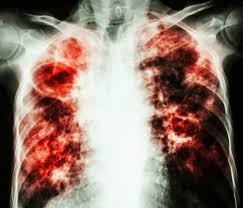

Tuberculosis, conjointly referred to as TB, could be a contagious microorganism infection which will be found nearly anyplace within the body, however is found most typically within the lungs. This as a result of the microorganism that's accountable for TB, Mycobacterium tuberculosis, is transmitted through the air because it doesn't thrive on surfaces. Though TB has been discovered over one hundred years past, it's still one in every of diseases that causes the foremost deaths annually. To urge a lot of insight why TB still exists at giant scale to the present, we have a tendency to should cross-check however TB works, wherever it's active and the way it are often treated at the instant.

Tuberculosis spreads via the air, which implies that the lungs are sometimes the primary places to be infected with the microorganism. The Mycobacterium tuberculosis is absorbed by white blood cells, however won't be lessened by them. The microorganism can keep dormant during this stage (Pulmonary TB), sometimes for a protracted time. Eventually, the microorganism can invade a white vegetative cell and multiply till the white vegetative cell dies and breaks open. A lot of TB microorganism can unfold from there and invest different cells, forming a tumor. By doing so that they usually jaunt different body-parts and this method of sitting within the white blood cells makes it tougher to urge them contacted with treatment. Moreover, since Mycobacterium tuberculosis is understood for growing slowly it should usually be neglected before it goes on to consequent stage, Secondary TB.